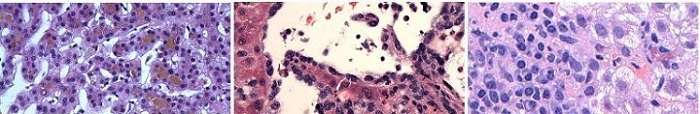

The hepatobiliary pathology service at UCLA provides rapid, high quality diagnostic histopathology for liver disease on both biopsy and resection material. Our Team has extensive experience with diagnosis of medical liver biopsies for children and adult. We also have extensive experience with neoplastic hepatobiliary disease. Of course as UCLA is one of the busiest liver transplant centers in the world, we have tremendous expertise in liver transplant pathology.